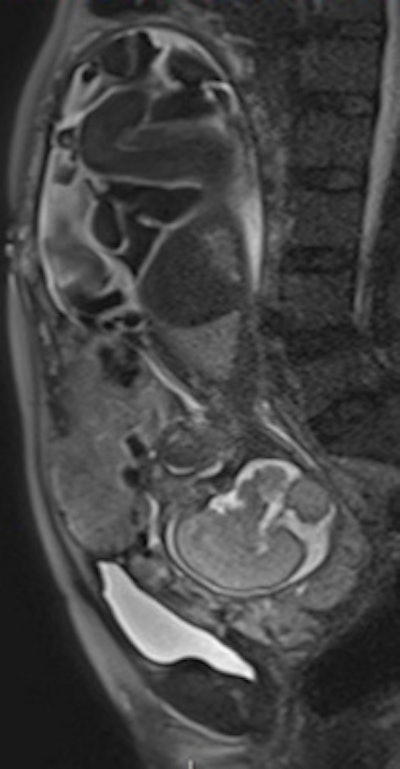

Sagittal T2-weighted single-shot fast spin-echo MR images show the placenta previa and evidence focal bulgings of the anterior uterine wall. The signal intensity of the placenta is heterogeneous, with presence of T2-hypointense placental bands. Observe the discontinuity of the myometrial layer, extending beyond the uterine serosa.The kappa values for interobserver agreement for detecting placental invasion were substantial (0.64) for seniors and moderate (0.41) for juniors. Seniors detected placental invasion and depth of infiltration with significantly higher diagnostic accuracy than juniors.